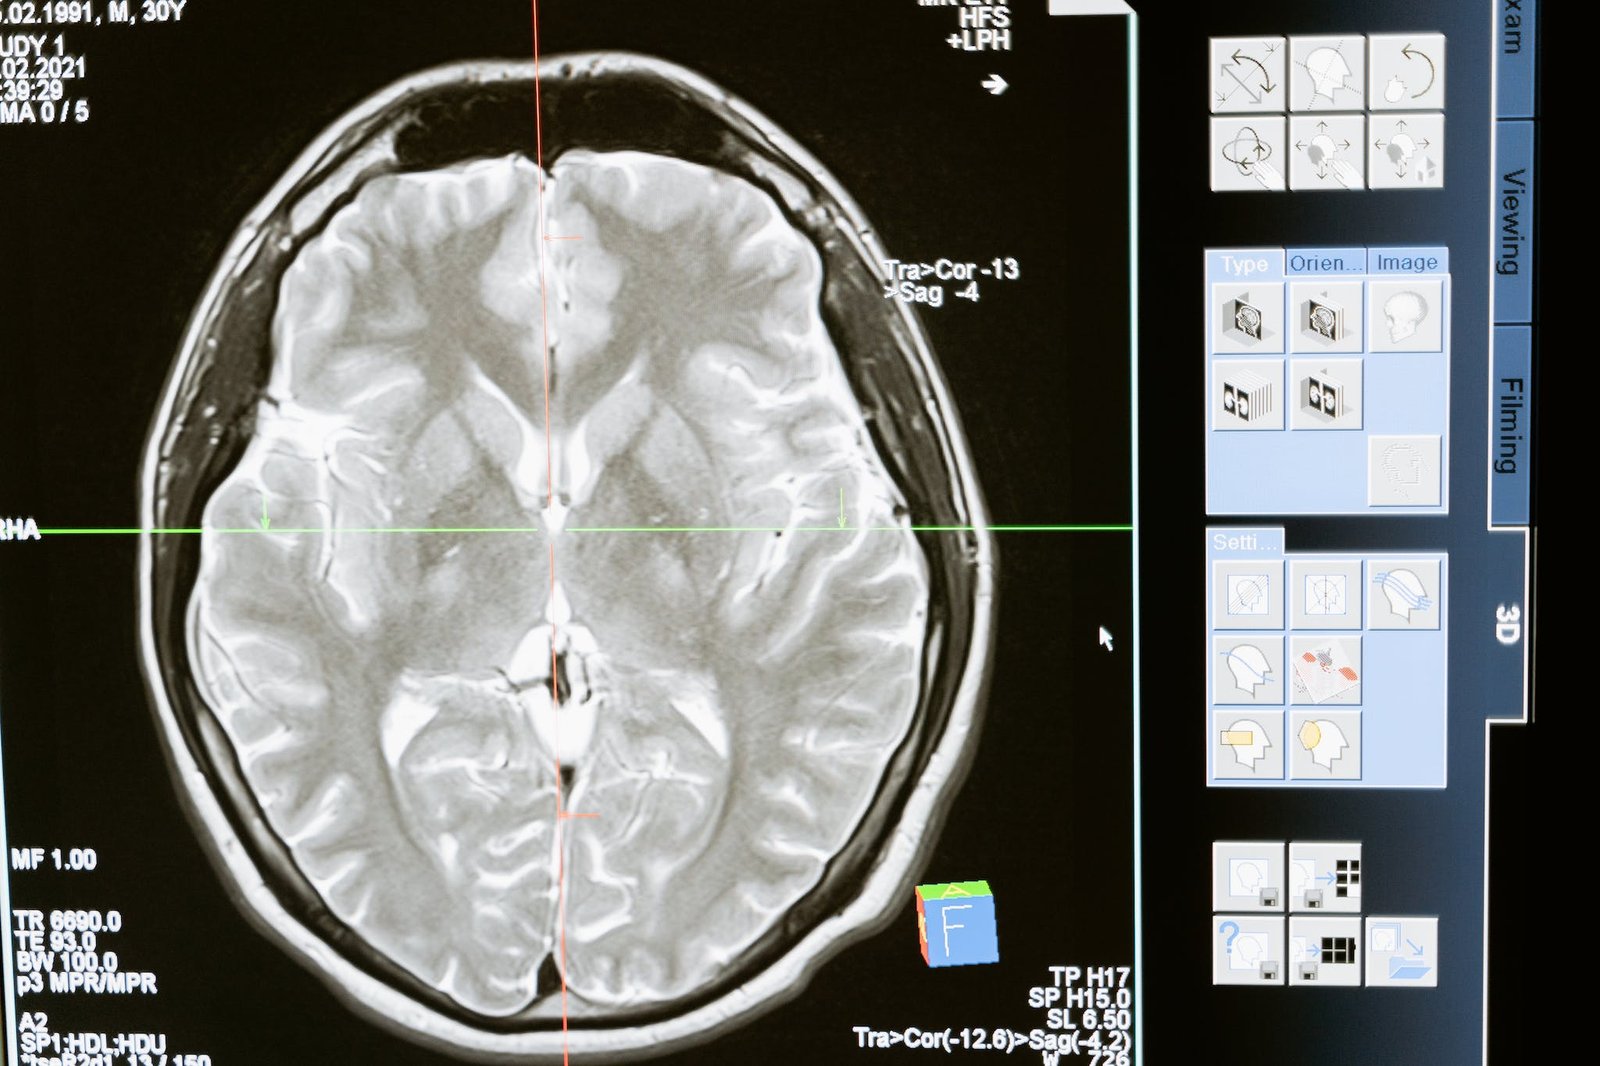

Brain

Anatomy & Physiology